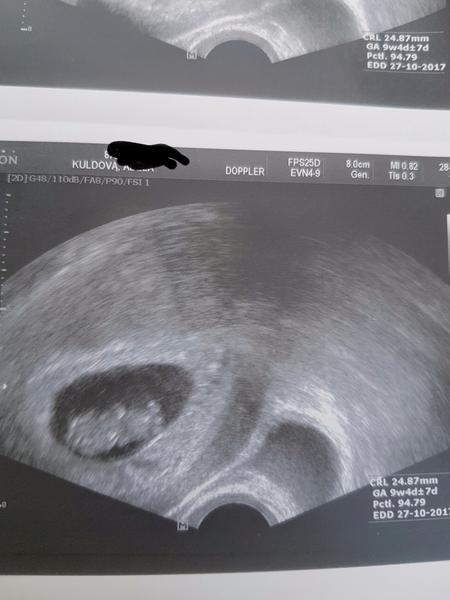

Ahoj, zatím je vše v pořádku. Embryjko má 7mm,takže vše v norněnorně. Hematom tam stále je, ale už se zahustil, tak doufám že už se zacnezačne vstřebává. Kontrola zase za týden. Čekala jsem hodinu než jsem přišla na řadu, srdce jsem měla až někde....🙂.